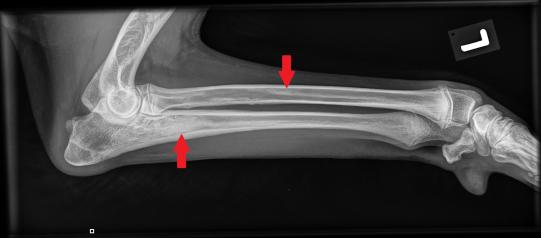

Beim Folgebesuch einige Tage später ist der Hund wieder ganz der alte - ungestüm, fröhlich und mit prächtigem Appetit gesegnet. In Sedation werden nun beide Vorderbeine geröntgt, um zu eruieren, was zu der wechselhaften Lahmheit geführt hatte.

Die typischerweise von Wachstumsstörungen betroffenen Gelenke (Ellbögen und Schultergelenke) erscheinen wie erhofft unauffällig. In sämtlichen Langknochen (Elle, Speiche, Oberarmknochen) beider Vorderbeine zeigen sich jedoch starke Veränderungen: Das Knocheninnere weist an verschiedenen Stellen fleckige Verdichtungen auf, welche die normale feine Knochenstruktur verdrängt haben. Die beobachteten Veränderungen sind typisch für eine sogenannte Panostitis. Die Besitzerin erhält einen Vorrat an Schmerzmitteln, falls das Problem wieder aufflammen sollte.